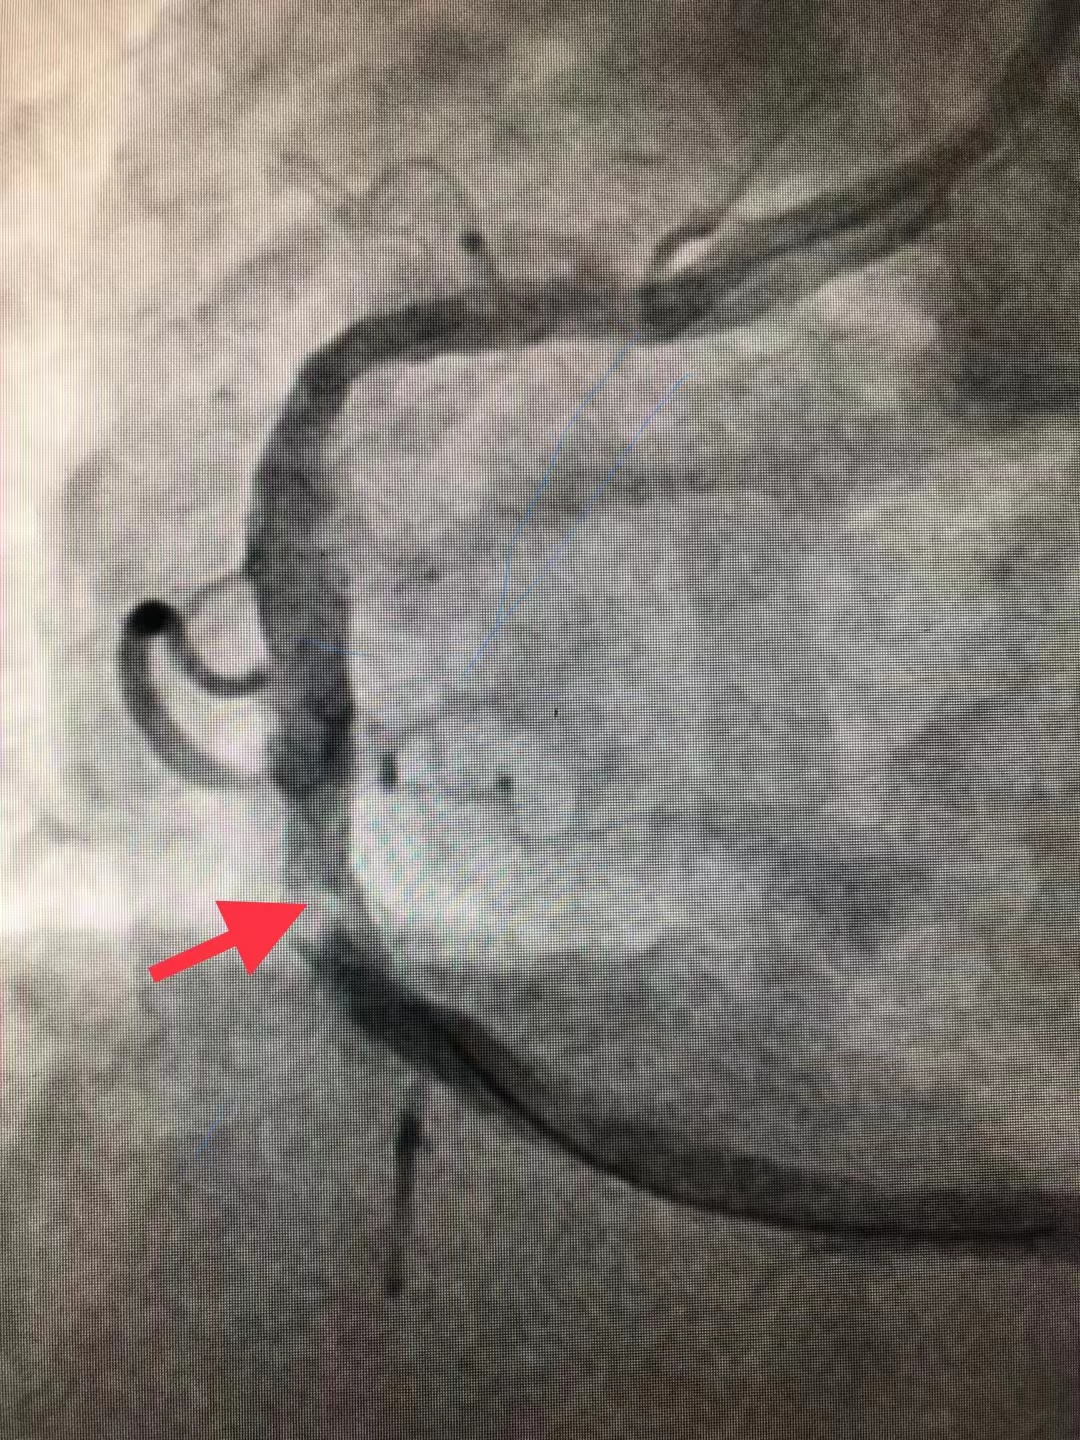

冠脉造影结果:LM外膜钙化,内膜不光滑,中段狭窄90%,TIMI3级。LCX外膜钙化,内膜不光滑,TIMI3级。RCA外膜钙化,内膜不光滑,近段狭窄80%,中段狭窄90%,可见破损斑块,TIMI3级。